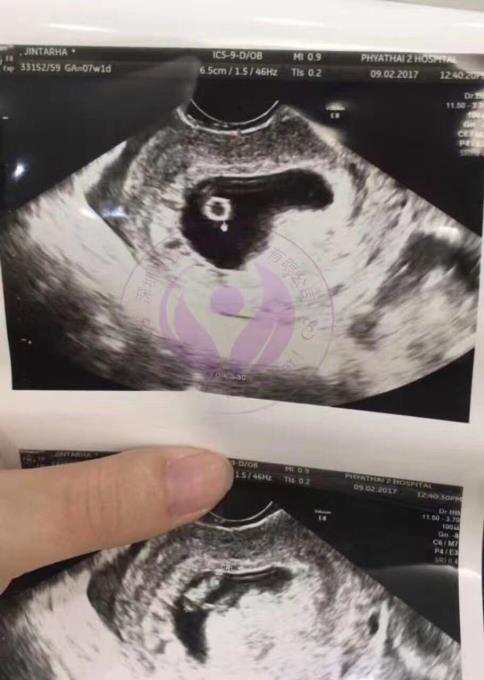

咱们两人成亲后就总是处于备孕状况,也不知晓什么原因总是都没有怀上,家里面也是总是在敦促着,这让咱们也是备受压力。因两人工作太忙时间感知不足用,紧随时间渐渐的流失2个才开启思想到再如此下去是不行的要否则都不知晓啥时候才能够有自身的宝贝。常常途经娱文场合看见那些孩童的欢声笑语心里也是雀跃的!在看见这类情景之余每每刺激着我,因而当时决议抽暇时间2个人去医院检验看看见底是啥弊端? 在医院检验后拿了报表单是我太太问题多囊卵巢,造成每个卵泡长大不能排卵,成熟的卵子就如此凋落了。知晓了症状后咱们就到处寻医,可**的结果还是没有多大成效,金钱耗费了不说还耗费了如此多时间耽搁了病情。经过这一系列的中转周折最终经同伙简介选取了去泰国做试管,在疗程中进展还算是较为顺遂的,咱们选取2015年末去的泰国,试管细节在这里就不说如此多啦,因本身是多囊胚胎也就多了,经判定还有5男8女的健康囊胚,这结果还是很满意的。因咱们工作原因还有我太太的肌体状况咱们选取了下次过来移植冷冻胚胎,因而咱们2个选取回国了。 在2016年5月选取移植了冷冻胚胎,高兴的是一次就顺利了不必再跑一趟了,这给咱们莫大的快慰。验孕顺利后回国咱们悉心呵护着这小宝贝每次全是根据医师吩咐定时产检,不敢怠慢了。这是产检第9周B超照片。